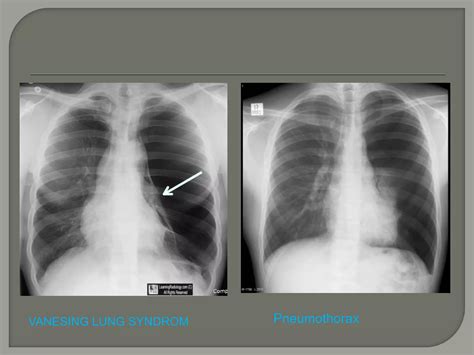

While often associated with emphysema, bullae can develop through various mechanisms. The lung tissue essentially loses its internal architecture, leading to areas of over-inflation. When these areas become large enough to compress healthy surrounding tissue, the condition is referred to as giant bullous emphysema, or Vanishing Lung Syndrome, in extreme cases.

Medical professionals categorize the severity of the disease based on the size of the bullae and the impact they have on the patient’s respiratory function. The table below outlines how these bullae are typically classified in clinical practice.

Classification Bulla Size Clinical Impact

Small Bullae 1–5 cm Minimal symptoms; usually stable.

Large Bullae 5–10 cm Noticeable breathlessness; potential compression.

Giant Bullae > 10 cm Severe, requiring urgent evaluation and potential surgery.

⚠️ Note: Always consult with a pulmonologist to undergo diagnostic imaging, such as a CT scan, as chest X-rays may not always reveal the full extent of the bullae.

Diagnostic Procedures

Diagnosis begins with a thorough medical history and physical examination. However, imaging is essential to confirm Bullous Lung Disease. High-resolution Computed Tomography (HRCT) is considered the gold standard for visualizing bullae. It allows physicians to determine if the bullae are localized or widespread and whether they are compressing functional lung tissue. Pulmonary function tests (PFTs) are also conducted to measure lung capacity and identify the degree of airflow obstruction.